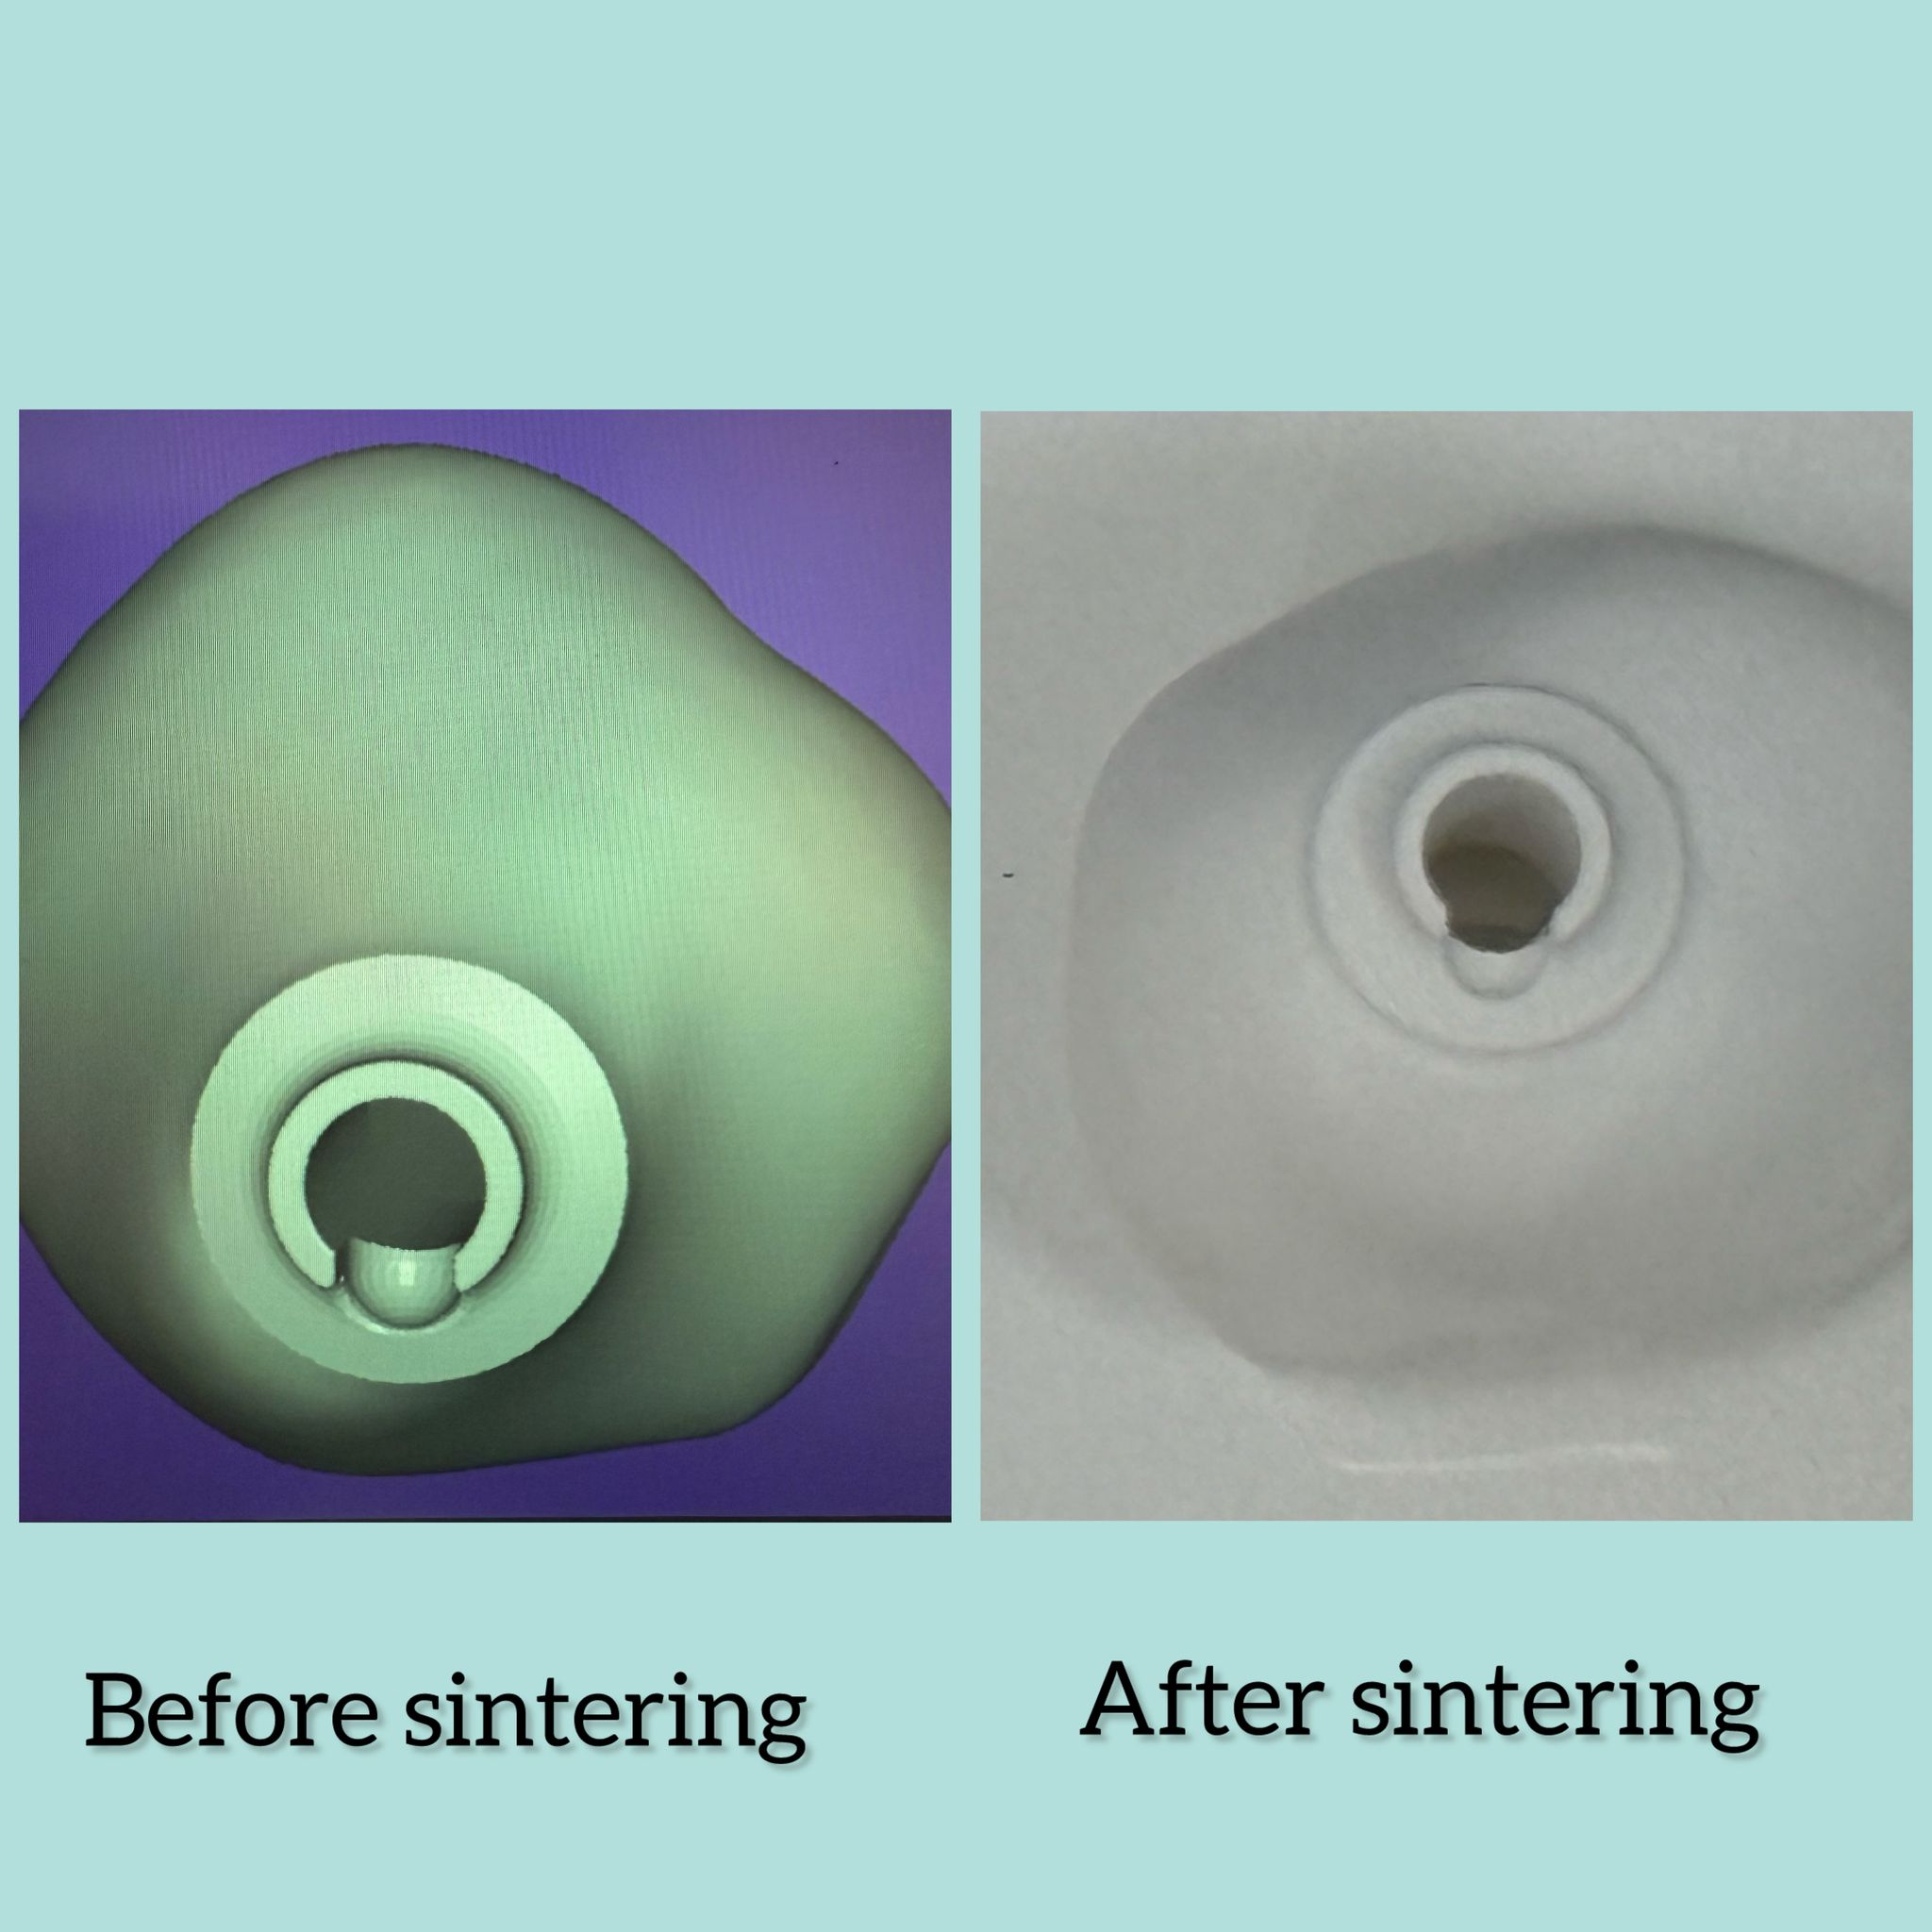

Dental Laboratorium in Amsterdam

Dental Laboratorium in Amsterdam